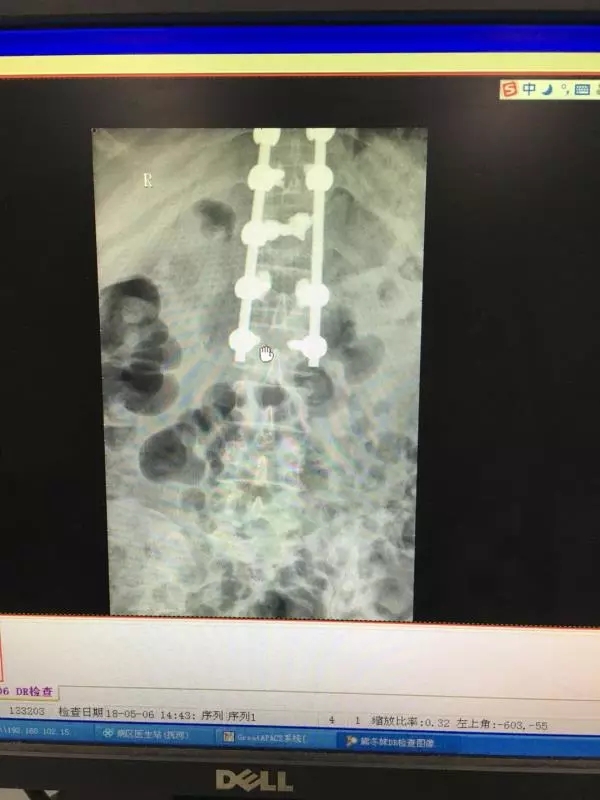

经皮椎弓根螺钉同样也是通过经皮做一小切口,利用C臂机作为医生的眼睛,依次进入导针,扩孔,后期进入椎弓根螺钉。操作稍有不慎,螺钉就可能进入椎管内,造成截瘫。如下图所示: